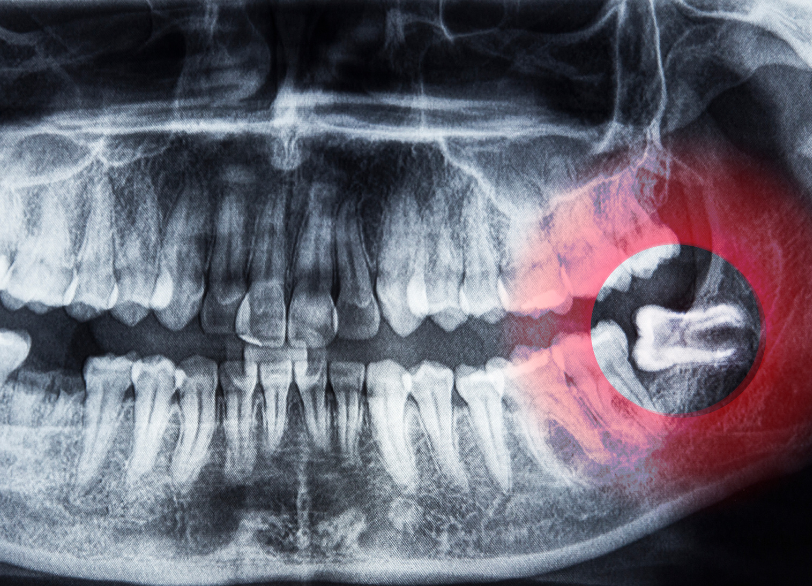

親知らずは専門的には「第三大臼歯」と呼ばれ、前歯から数えて8番目、一番奥に生えてくる永久歯です。多くの場合、10代後半から20代前半頃に生え始めますが現代人は食生活の変化などから顎が小さくなる傾向にあり、親知らずがきちんと生えるためのスペースが不足していることがほとんどです。

そのため横向きや斜めに傾いて生えたり、骨の中に完全に埋まったままだったりと正常な位置に生えてこられないケースが非常に多く見られます。

すべては「正確な診断」から始まります – 歯科用CTの活用

安全な抜歯を行う上で最も重要なのが、術前の精密な診査・診断です。特に下顎の骨の中には「下歯槽神経(かしそうしんけい)」という下唇の感覚などを司る太い神経が通っています。

親知らずの根の先がこの神経に近接している、あるいは接触しているケースも珍しくありません。

当院ではこのような複雑なケースや骨の中に深く埋まっている親知らずの抜歯を行う際には、必ず「歯科用CT」による撮影を行います。

従来の平面的なレントゲン写真では分からなかった親知らずの根の立体的な形や、神経・血管との正確な位置関係を三次元的に把握することができます。

このCTによる詳細な情報が手術中の神経損傷などの偶発的な事故を未然に防ぎ、安全で確実な抜歯計画を立てるための絶対的な基盤となるのです。